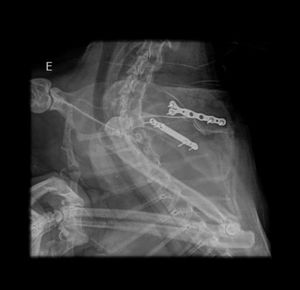

Oi gente, essa é minha gatinha Shabyska. Minha companheirinha, que ficou comigo por quase 10 anos, mas infelizmente foi atacada por cães, teve várias perfurações pelo corpo, trauma na mandíbula e fratura na escápula. Ela teve que passar por cirurgia para a colocação de duas placas na escápula e sonda esofágica para alimentação, pois não conseguia mover a mandíbula. Cinco dias após o procedimento anterior, ela apresentou um quadro de dificuldade respiratória o que a levou a ter de fazer uma cirurgia de herniorrafia diafragmática, mas no pós operatório ela teve uma descompensação respiratória e infelizmente veio a óbito. Perdi minha Shabyska e preciso da sua ajuda para pagar as despesas médicas pois ficaram altissimas e infelizmente não estou conseguindo arcar com tudo sozinha, além de não ter obtido ajuda do responsável pelos cachorros.Você pode me ajudar? Obrigada!